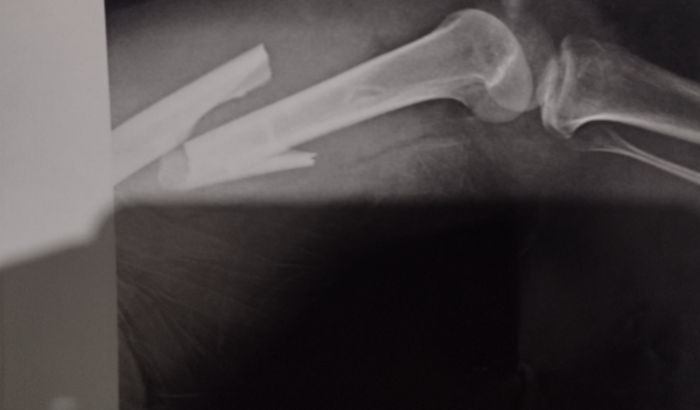

Ele quebrou o fêmur e o joelho, passando já por 2 cirurgias e colocando gaiola e pinos para conseguir ir para casa. E está imobilizado, dependendo agora de muita ajuda e auxílio para se locomover, comprar medicações e daqui alguns dias passar por uma nova cirurgia. Como conhecemos a família e sabemos o quanto são trabalhadores e de todas as suas lutas, fizemos essa vaquinha para auxiliar com o valor que cada um conseguir e tocar no coração, para a ajuda de medicações, auxílio aos filhos do Henrique e durante o processo de todo tratamento que pode vir demorar de 6 a 9 meses, para ele voltar a todas as atividades normais. E estamos orando muito para isso!